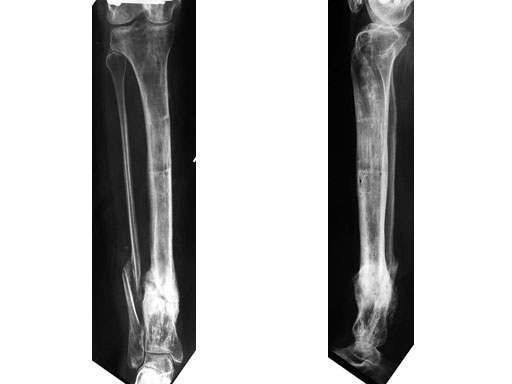

A 33-year-old female sustained a grade III open fracture of the right lower leg.

Case provided by Michael Raschke, Mnster, DE